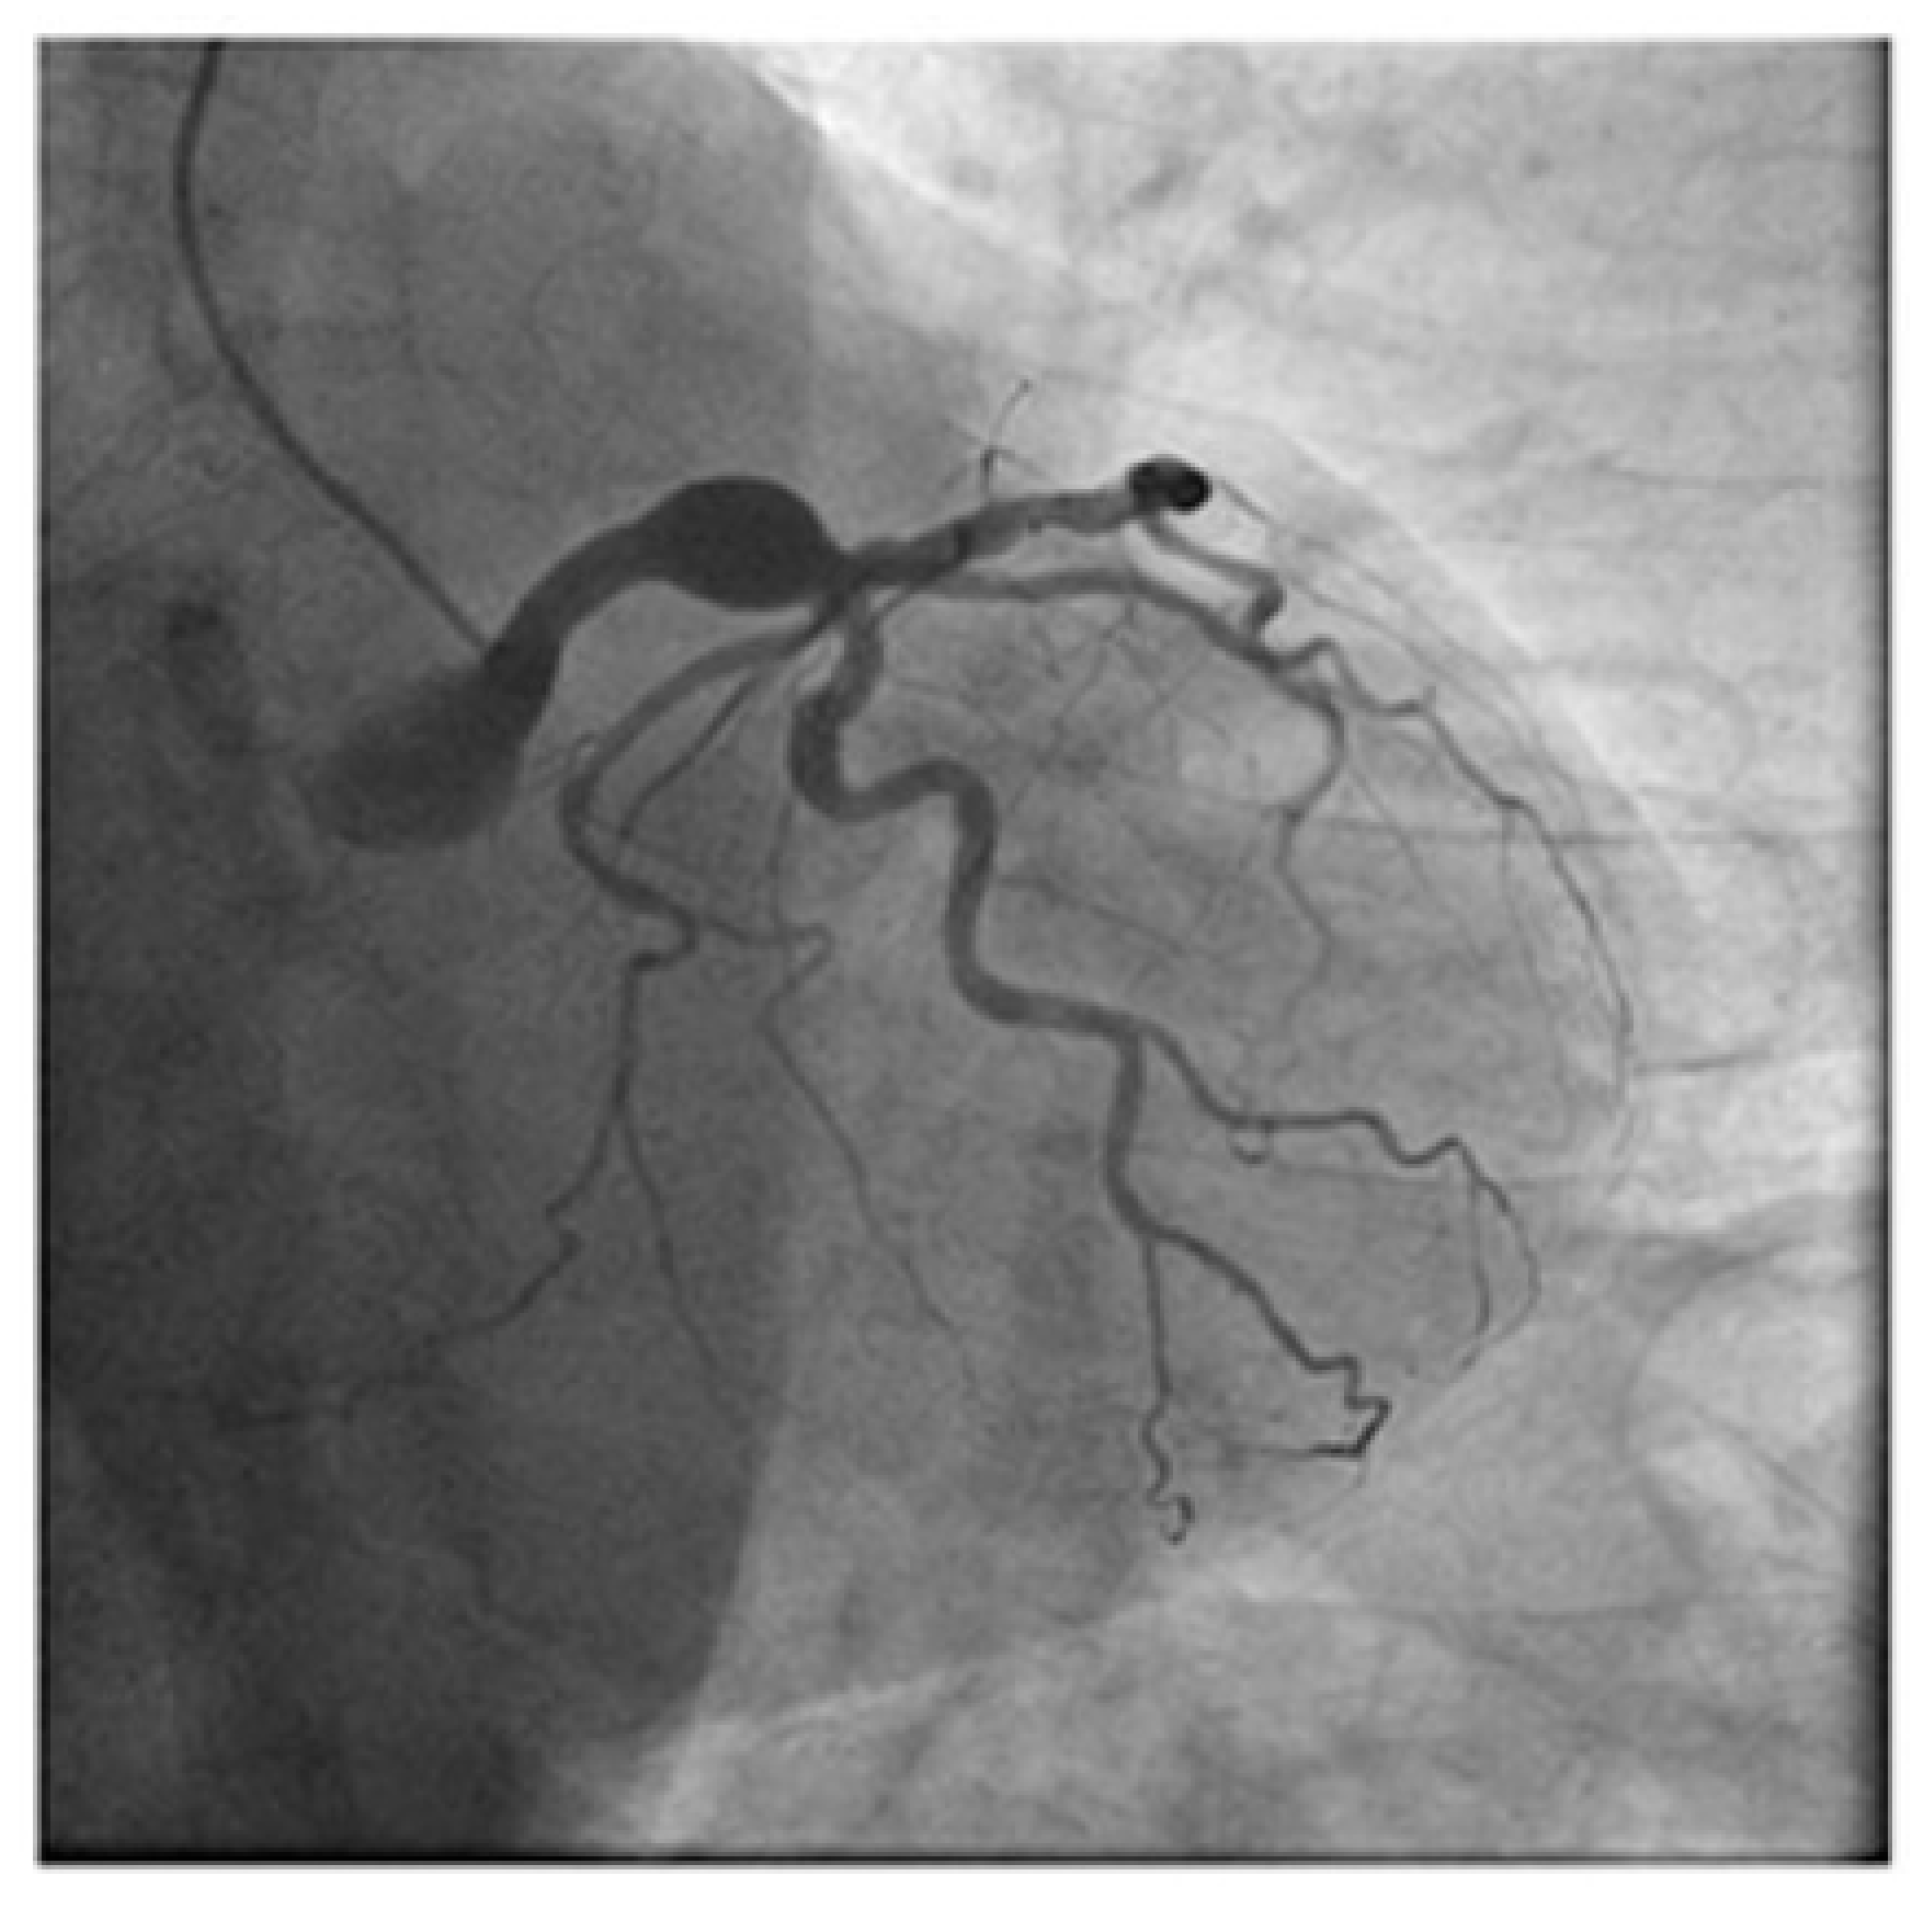

1.1. Diagnostic